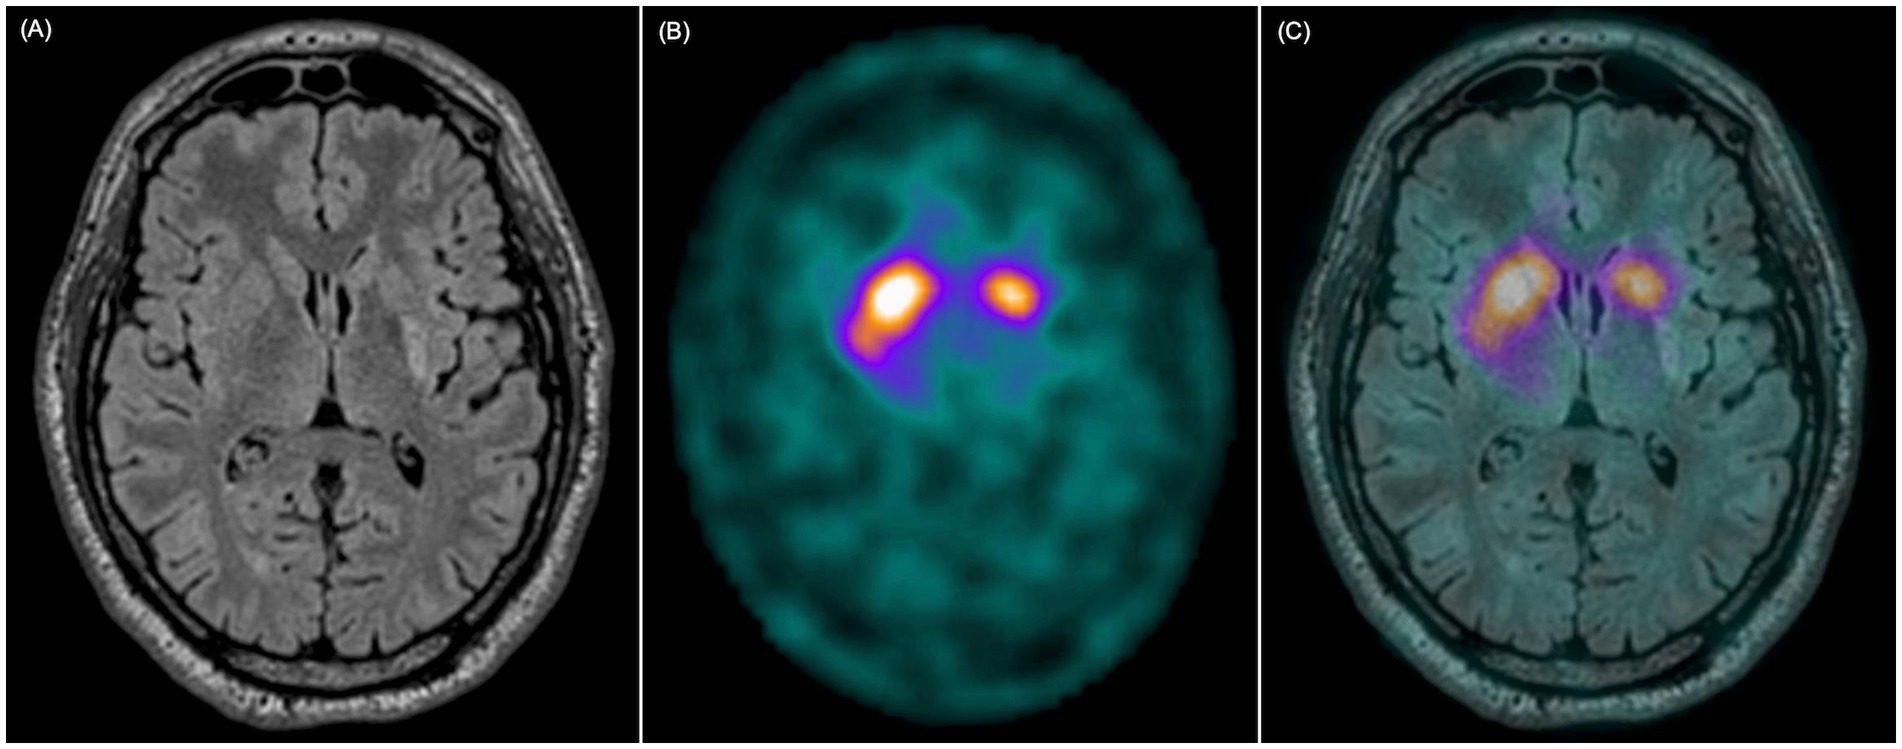

All patients showed reduced radiotracer uptake on [123I]FP-CIT SPECT at the stroke lesion site based on the visual evaluation (Figure 3). According to semi-quantitative regional analysis, 11/15 patients (73%) had abnormal SPECT imaging (Z-score ≤ −2 in at least one area), of which all included the posterior putamen. 8/10 patients with parkinsonism and 3/5 patients without parkinsonism at 1 year had abnormal semi-quantitative SPECT binding (Table 5). The Z-score was significantly lower on the infarcted side (p < 0.001), and it was lower in the putamen for patients with parkinsonism compared to those without (Table A2). There was a significant correlation between SPECT Z-score and infarct volume proportion for the striatum, indicating that the volume of the structural damage was coupled with the degree of dopamine deficit. However, there was no significant correlation between the MDS-UPDRS III score and striatal Z-scores for the striatum as a whole or for the posterior putamen (Table A3).

Figure 3

MRI and [123I]FP-CIT SPECT in a patient with an isolated striatal infarct. (A) T2-FLAIR weighted image shows infarct in the left posterior putamen. (B) [123I]FP-CIT SPECT shows reduced ligand uptake in the left posterior putamen. (C) Fusion of MRI and [123I]FP-CIT SPECT shows that the reduced ligand uptake closely follows the limits of the vascular lesion.

All our patients had infarcts in the posterior putamen and reduced [123I]FP-CIT uptake in the same area (Figure 3), a region typically affected in PD. Although all patients showed reduced uptake on visual inspection, only 73% met the Z-score threshold for abnormality in DaTQuant. This discrepancy likely reflects the limitations of applying standardized Z-scores, developed for diffuse neurodegenerative conditions affecting entire anatomical regions, to focal infarcts involving only part of the striatum. As a result, DaTQuant may underestimate abnormalities in small, localized lesions such as those observed in this study. A representative case example illustrating this limitation is shown in Supplementary Figure 1. Notably, there was an apparent mismatch between imaging and clinical findings - i.e. reduced [123I]FP-CIT binding in some patients without clear parkinsonian symptoms. [123I]FP-CIT SPECT reflects presynaptic dopaminergic integrity, but not clinical expression, and a similar disconnect is well-documented in early PD, where abnormal scans can precede symptom onset (30, 31). In this context, the imaging confirms that the nigrostriatal pathway was structurally affected, even if clinical manifestations had not yet emerged. Longitudinal follow-up is needed to clarify whether these patients later develop symptoms.